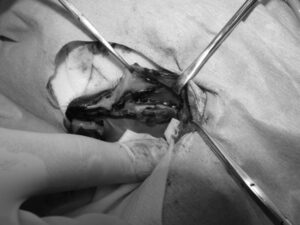

重度の歯周病で両側の下顎の病的骨折をしているワンちゃんが来院されました。悪い歯の抜歯と下顎のプレート固定(TITAN LOCK1.2mm使用)で対応しました。退院後しっかりご飯が食べられるようになりました。よかったね。